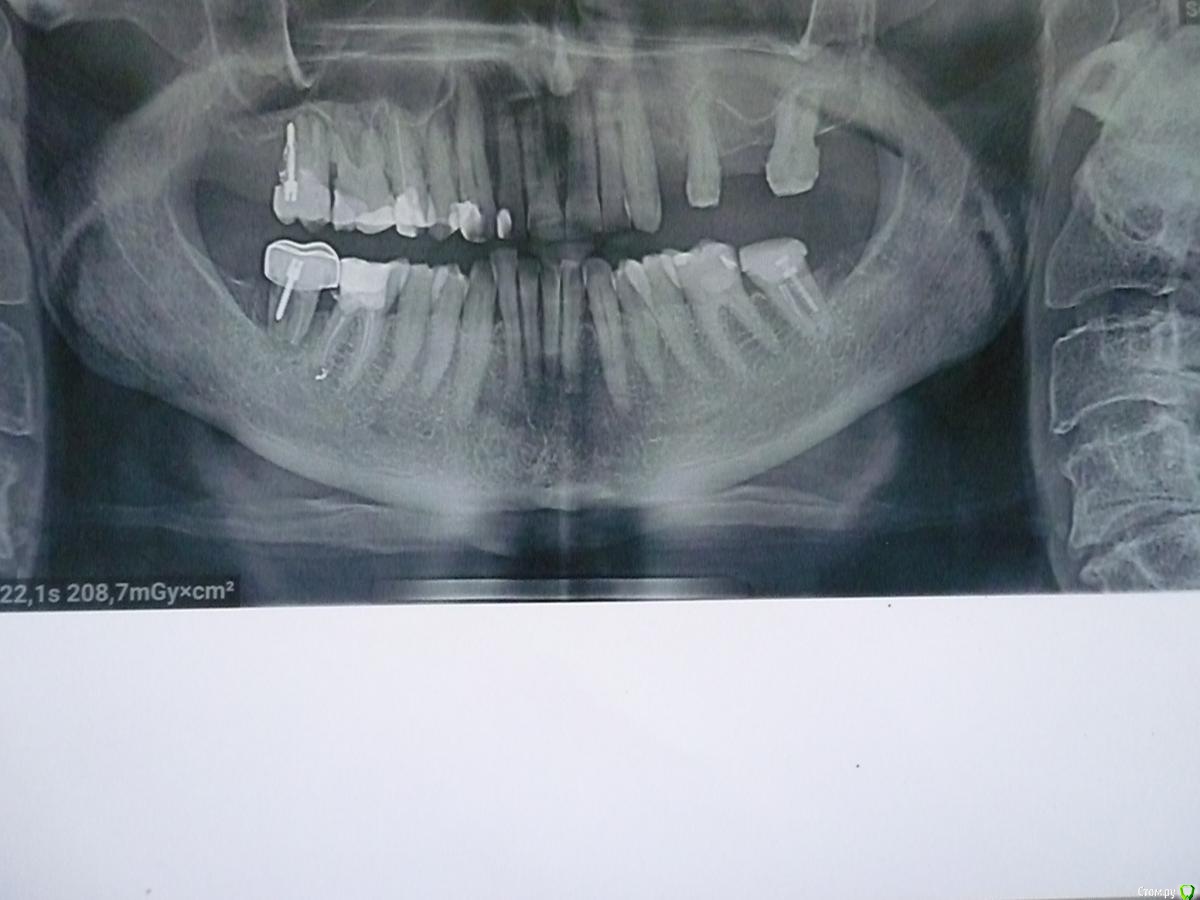

Уважаемые стоматологи! Помогите пожалуйста принять правильное решение НАДО ЛИ УДАЛЯТЬ КРАЙНИЙ ВЕРХНИЙ ЗУБ с ПРАВОЙ СТОРОНЫ.

1)    только удаление т.к. анкер стоит «снаружи» и  "ушла" кость.

2)     «сто лет» так было и еще столько же простоит, а если будет беспокоить, то удалить, что не критично т.к. стоящий перед ним зуб еще «живой», есть шанс его сохранить и тем самым сохранить справа свои жевательные зубы.

Зуб не беспокоит, но тревожит, что при удалении может быть нарушен, стоящий перед ним зуб.

И еще вопрос -  если этот крайний зуб сейчас не удалять, то какие НЕГАТИВНЫЕ ПОСЛЕДСТВИЯ могут быть.